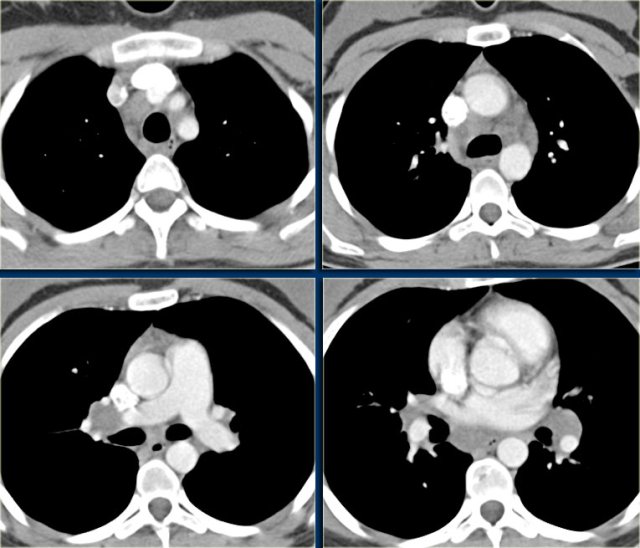

Non-Hodgkin lymphoma Non-Hodgkin lymphoma

Non-Hodgkin lymphoma

Non-Hodgkin disease in children occurs in the first and second decade of life.

The disease usually involves the nodes in the chest (paratracheal, subcarinal and hilar).

The extension of the disease is not contiguous, it can skip a location.

Non-Hodgkin disease, in contrast to Hodgkin disease, often spares the thymus.

In this case, enlarged lymph nodes are seen in the right paratracheal , hilar and subcarinal areas.